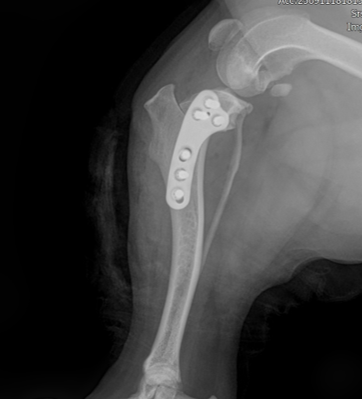

회전한 뼈가 움직이지 않도록 TPLO plate와 screws로 단단하게 고정해 뼈가 안정적으로 붙을 수 있게 합니다.

.png)

수술후 방사선 영상

5.예후

수술 후 방사선 평가에서는 수술 전 TPA 30°였던 것이 수술 후 4.7°로 교정되어 목표 범위에 가깝고, tibia의 전반적인 정렬도 계획대로 양호하게 확인되었고 절골면이 서로 잘 맞닿아 있었고, 과도한 틈이나 어긋남 없이 양호한 접촉 상태였습니다.